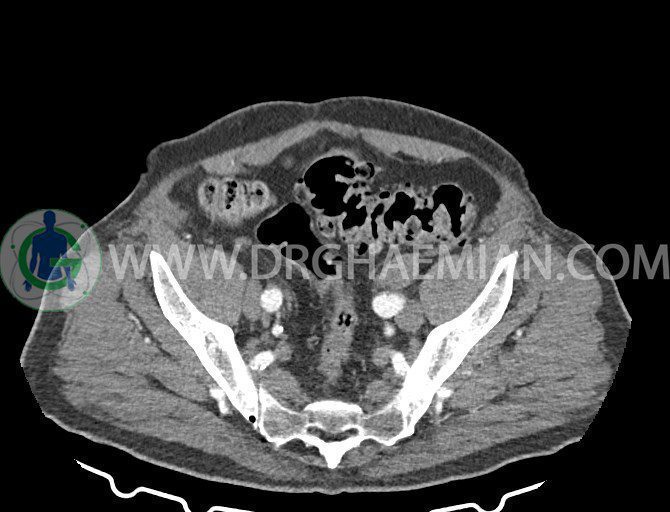

سی تی اسکن لگن یکی از روش های تصویربرداری با سی تی اسکن است. این روش با استفاده از تشعشعات تصاویر عرضی از ناحیه شکمی ایجاد میکند. در این کیس ديورتيكولوزيس، کیست های کورتیکال در هر دو کلیه، لنفادنوپاتی، کلسیفیکاسیون دیواره آئورت و شریان ایلیاک، تغییرات DJD ناحیه توراکولومبار و پروستات بزرگتر از عادی دیده می شود.

در سي تي اسکن اسپيرال شکم و لگن با و بدون کنتراست خوراکی و وريدی (مولتي ديدکتور 16 با مقاطع ظريف و بازسازي هاي ساژيتال و کرونال):

– کلسيفيکاسيون ديواره آئورت و شريان ها ايلياک همراه با نشانه هاي ترومبوز مورال در بيفورکاسيون ائورت با امتداد به پروگزيمال هاي شريان هاي ايلياک

لنفادنوپاتي به ابعاد mm 22 x 25 مجاور شريان ايلياک خارجي چپ و به ابعاد mm 17 x 28 مجاور شريان ايلياک خارجي راست

– پروستات به ابعاد mm 45 x 54، بزرگ تر از نرمال

مشهود است.